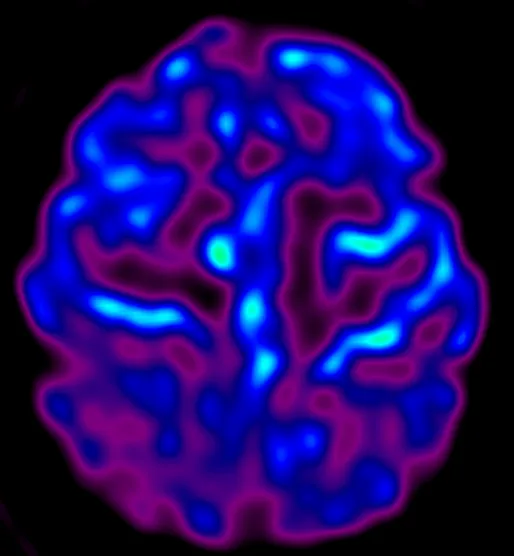

Dementia affects nearly 1 million people in the UK—stealing memories, independence, and time with loved ones. But right here in our community, Cobalt is changing that, by using advanced MRI and PET/CT scans to provide early, accurate diagnosis and also determine the effectiveness of treatment.

Dementia devastates lives—stealing memories, independence, and connections. Despite affecting nearly 1 million people in the UK, the diagnosis is often missed, and research is still underfunded. Cobalt tackles this problem with advanced brain imaging and research that leads to earlier, more accurate diagnoses and better treatments—offering families clarity, support, and hope for a different future.

Cobalt bridges the gap between diagnosis,treatment and the continued search for a cure. Using our cutting-edge MRI technology and the only PET/CT scanner in the 3 counties, we can detect dementia earlier and more accurately—especially in complex cases. Working with the NHS and researchers, we drive new clinical trials and vital discoveries. With your support, we can speed up diagnosis, unlock treatments, and train the specialists shaping the future of dementia care.